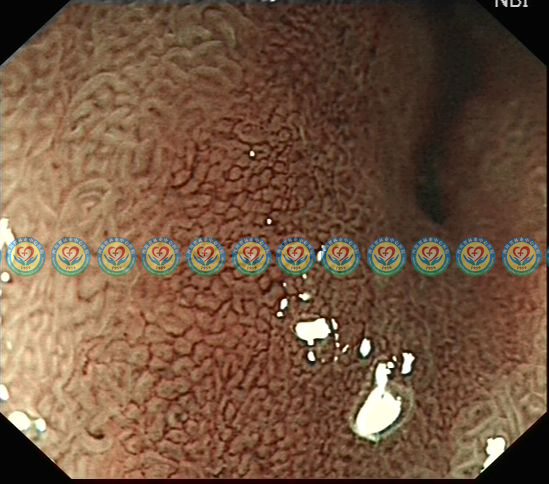

进一步放大观察,见病灶表面微血管类似网格样改变,符合分化型早癌改变

第二次取活检:灶性腺体高级别上皮内瘤变、粘膜内癌形成